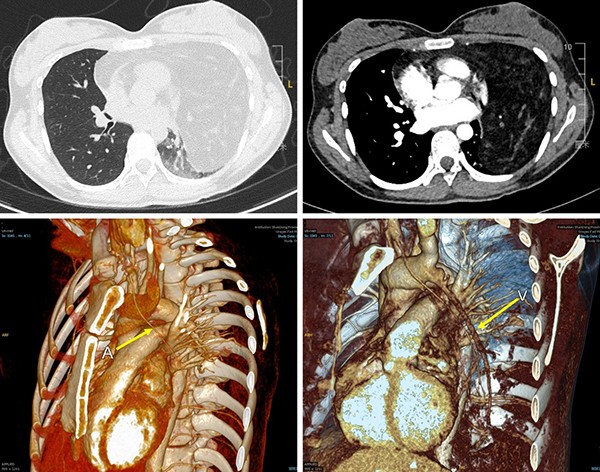

患者入院后复查胸部强化CT,结果显示前中纵隔混杂密度肿块,大部分凸向左例胸腔,最大截面接近20cm,包绕心脏、升主动脉及肺动脉等重要组织器官,左肺受压,体积缩小几不可见。同时,术前影像重建显示,肿瘤滋养动脉起自右头臂干,静脉血管回流至左无名静脉,均属两支重要血管。患者纵隔肿瘤瘤体巨大,国内外均属罕见。肿瘤消耗使患者血红蛋白、白蛋白等营养指标均低于正常值,且患者左侧肺脏长期不张、心脏长期受压,如果不尽快手术,肿瘤带来的风险将越来越高。

胸部增强CT示:前中纵隔及左侧胸腔可见巨大混杂密度肿块,最大截面约16.9x13.21cm,包绕心脏,升主动脉及肺动脉。血管重建示异常动静脉血供来源(黄色箭头指示)。